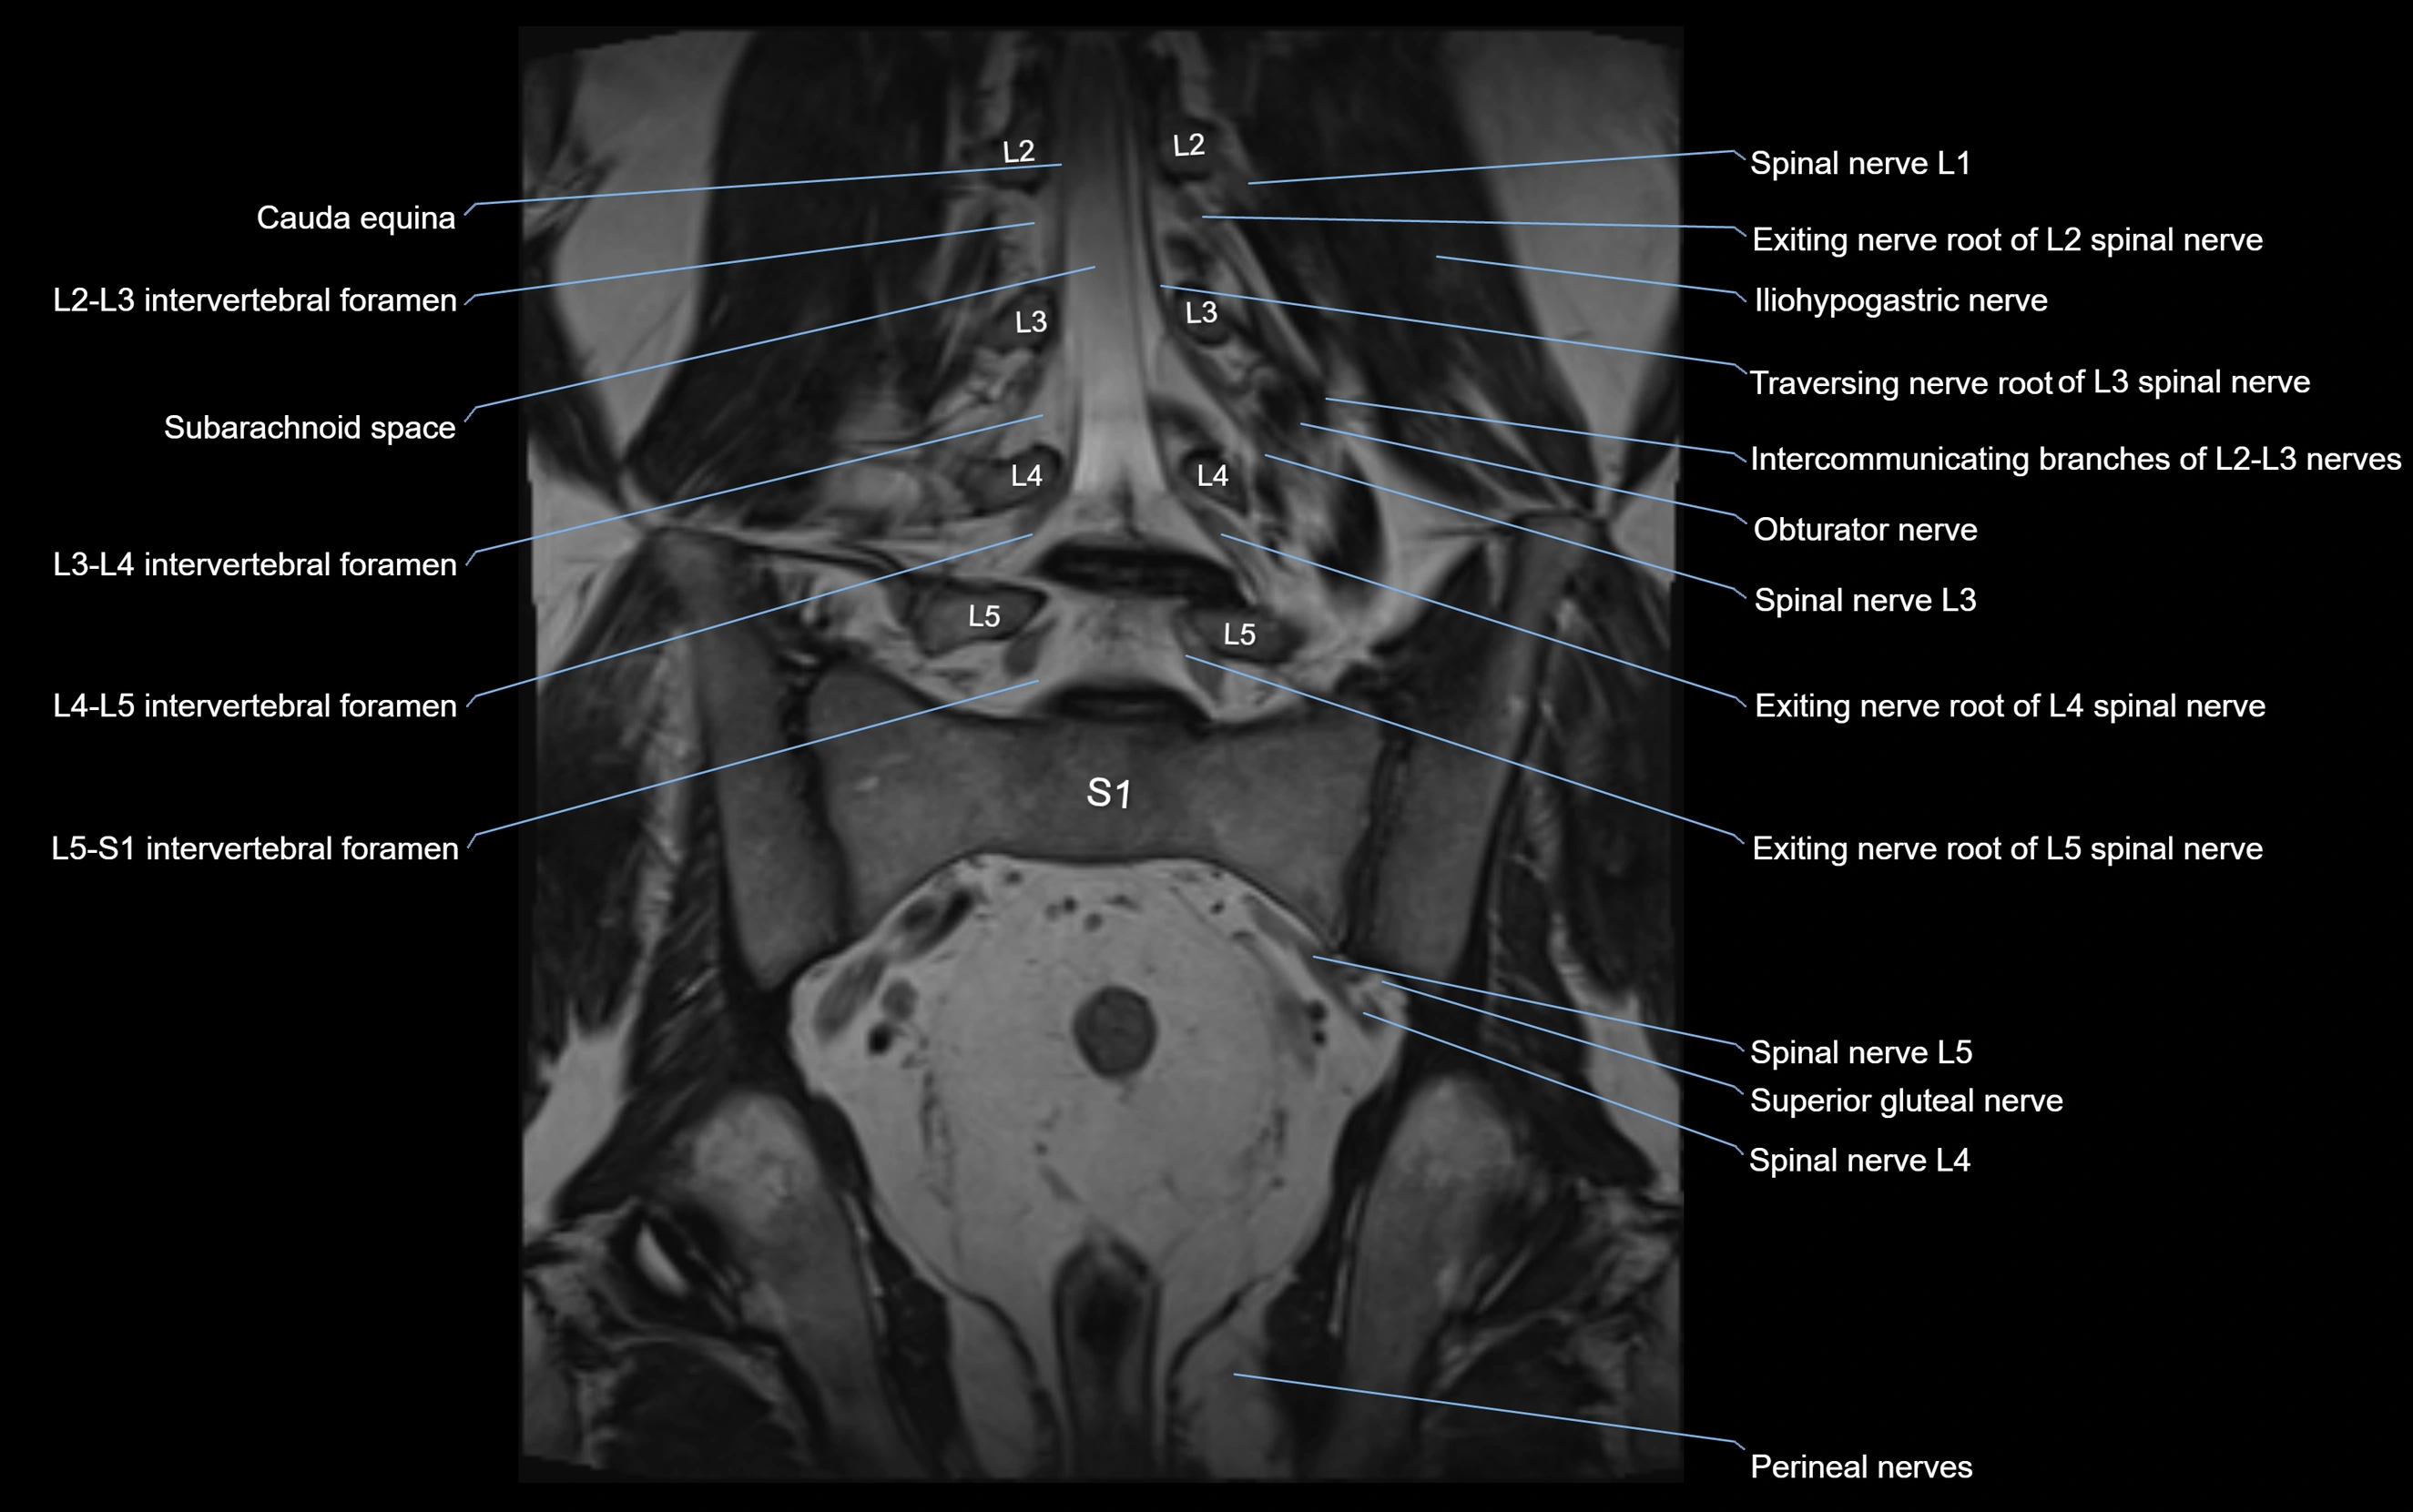

MRI image

image